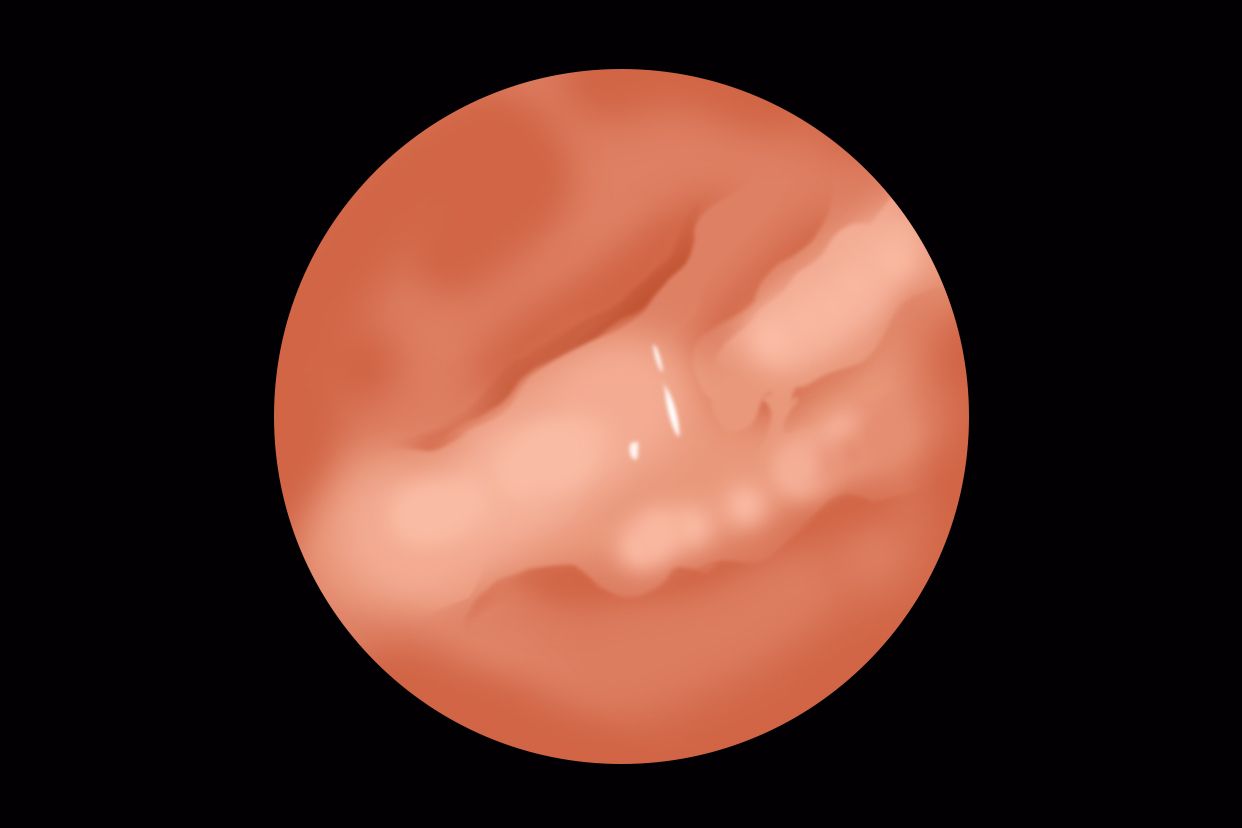

下消化道属于人体的消化器官,具体指的是十二指肠以下的部位,主要器官由空肠、回肠和大肠组成。

空肠和回肠的主要功能是消化和吸收食物,两者均属于小肠。大肠包括结肠、直肠、盲肠及阑尾。大肠的功能主要是吸收水分和电解质,形成、储存及排泄粪便,吸收少量水、无机盐和部分维生素。